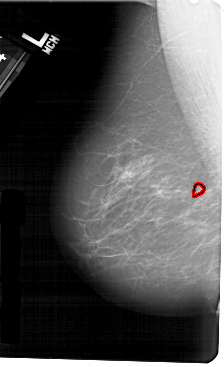

A_1278_1.LEFT_MLO

LEFT_MLO LINES 5491 PIXELS_PER_LINE 3346 BITS_PER_PIXEL 12 RESOLUTION 43.5 OVERLAY

FILE: A_1278_1.LEFT_MLO.OVERLAY

TOTAL_ABNORMALITIES 1

ABNORMALITY 1

LESION_TYPE CALCIFICATION TYPE PUNCTATE DISTRIBUTION CLUSTERED

LESION_TYPE MASS SHAPE OVAL MARGINS ILL_DEFINED

ASSESSMENT 4

SUBTLETY 2

PATHOLOGY BENIGN

TOTAL_OUTLINES 1

BOUNDARY